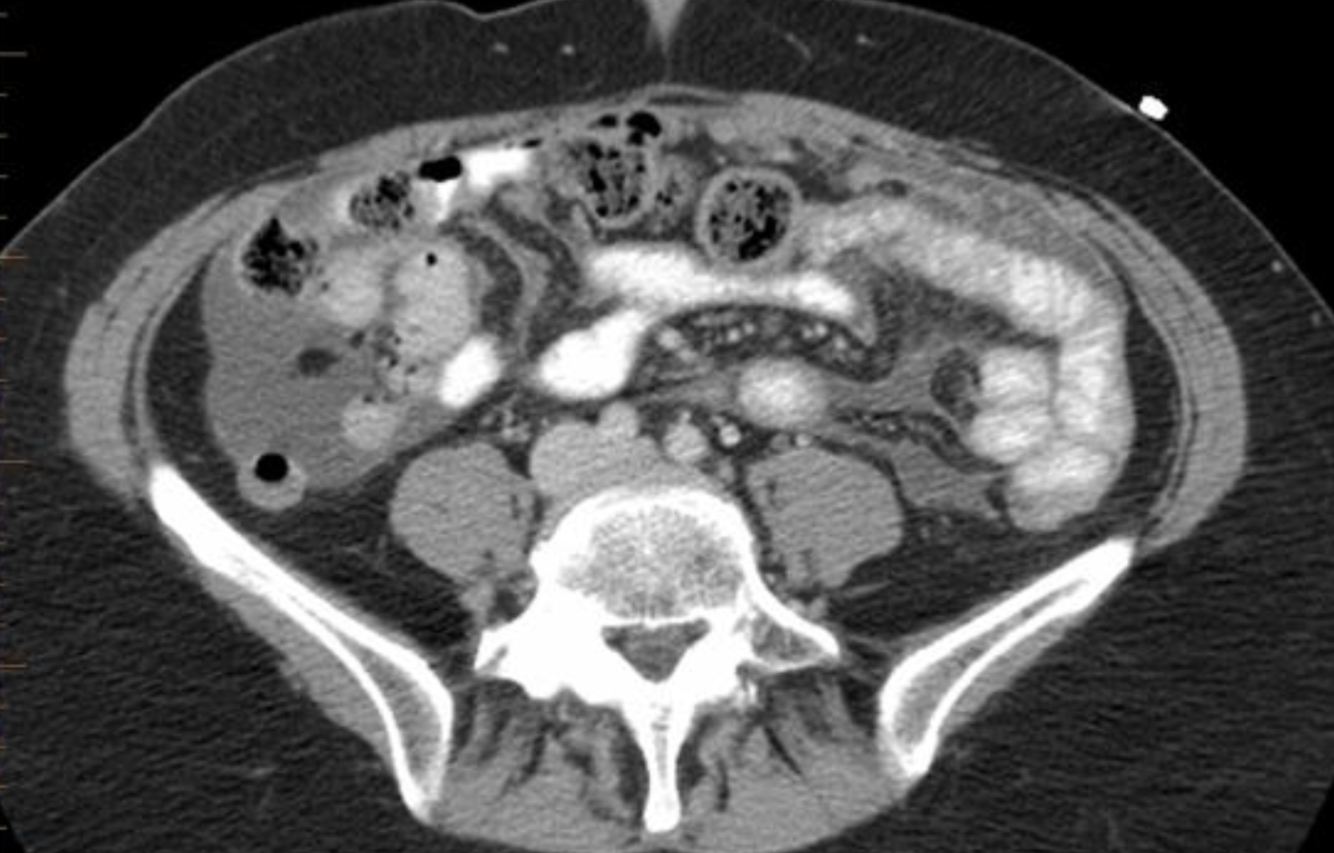

what is this?

who does it tend to occur in?

where does it tend to occur?

DDx?

Desmoplastic small round cell tumor

- aggressive malignancy usually occurring in adolescents and young adults

- CT shows multiple peritoneal-based soft tissue masses with necrosis and hemorrhage.

- Hematogenous or serosal liver mets can be present without a detectable primary tumor

- Desmoplastic small round cell tumours of the peritoneum are a rare and highly aggressive primary peritoneal malignancy.

- Epidemiology

- Desmoplastic small round cell tumour is usually seen in young adolescents and have a male predominance with a mean survival of 2-3 years.

- Clinical presentation

- A desmoplastic small round cell tumour usually presents with a palpable abdominal mass and abdominal distension with discomfort.

- It is most commonly seen to arise from the pelvic peritoneal cavity, the retrovesical or rectouterine space being the most frequent locations. The tunica vaginalis of the testis is the next most common location.

- Solitary or multiple soft tissue masses are seen with no definite organ of origin, usually in the retrovesical or rectouterine space, which enhance heterogeneously on contrast studies. Necrosis, haemorrhage and fibrous components are common.

- Peritoneal seeding, lymph nodal involvement, liver and bone metastases are common modes of spread.

Differential diagnosis

- peritoneal carcinomatosis

- non-Hodgkin lymphoma

- malignant peritoneal mesothelioma

- rhabdomyosarcoma

- See also

- small round blue cell tumours

https://epos.myesr.org/posterimage/esr/ecr2018/143415/mediagallery/753353